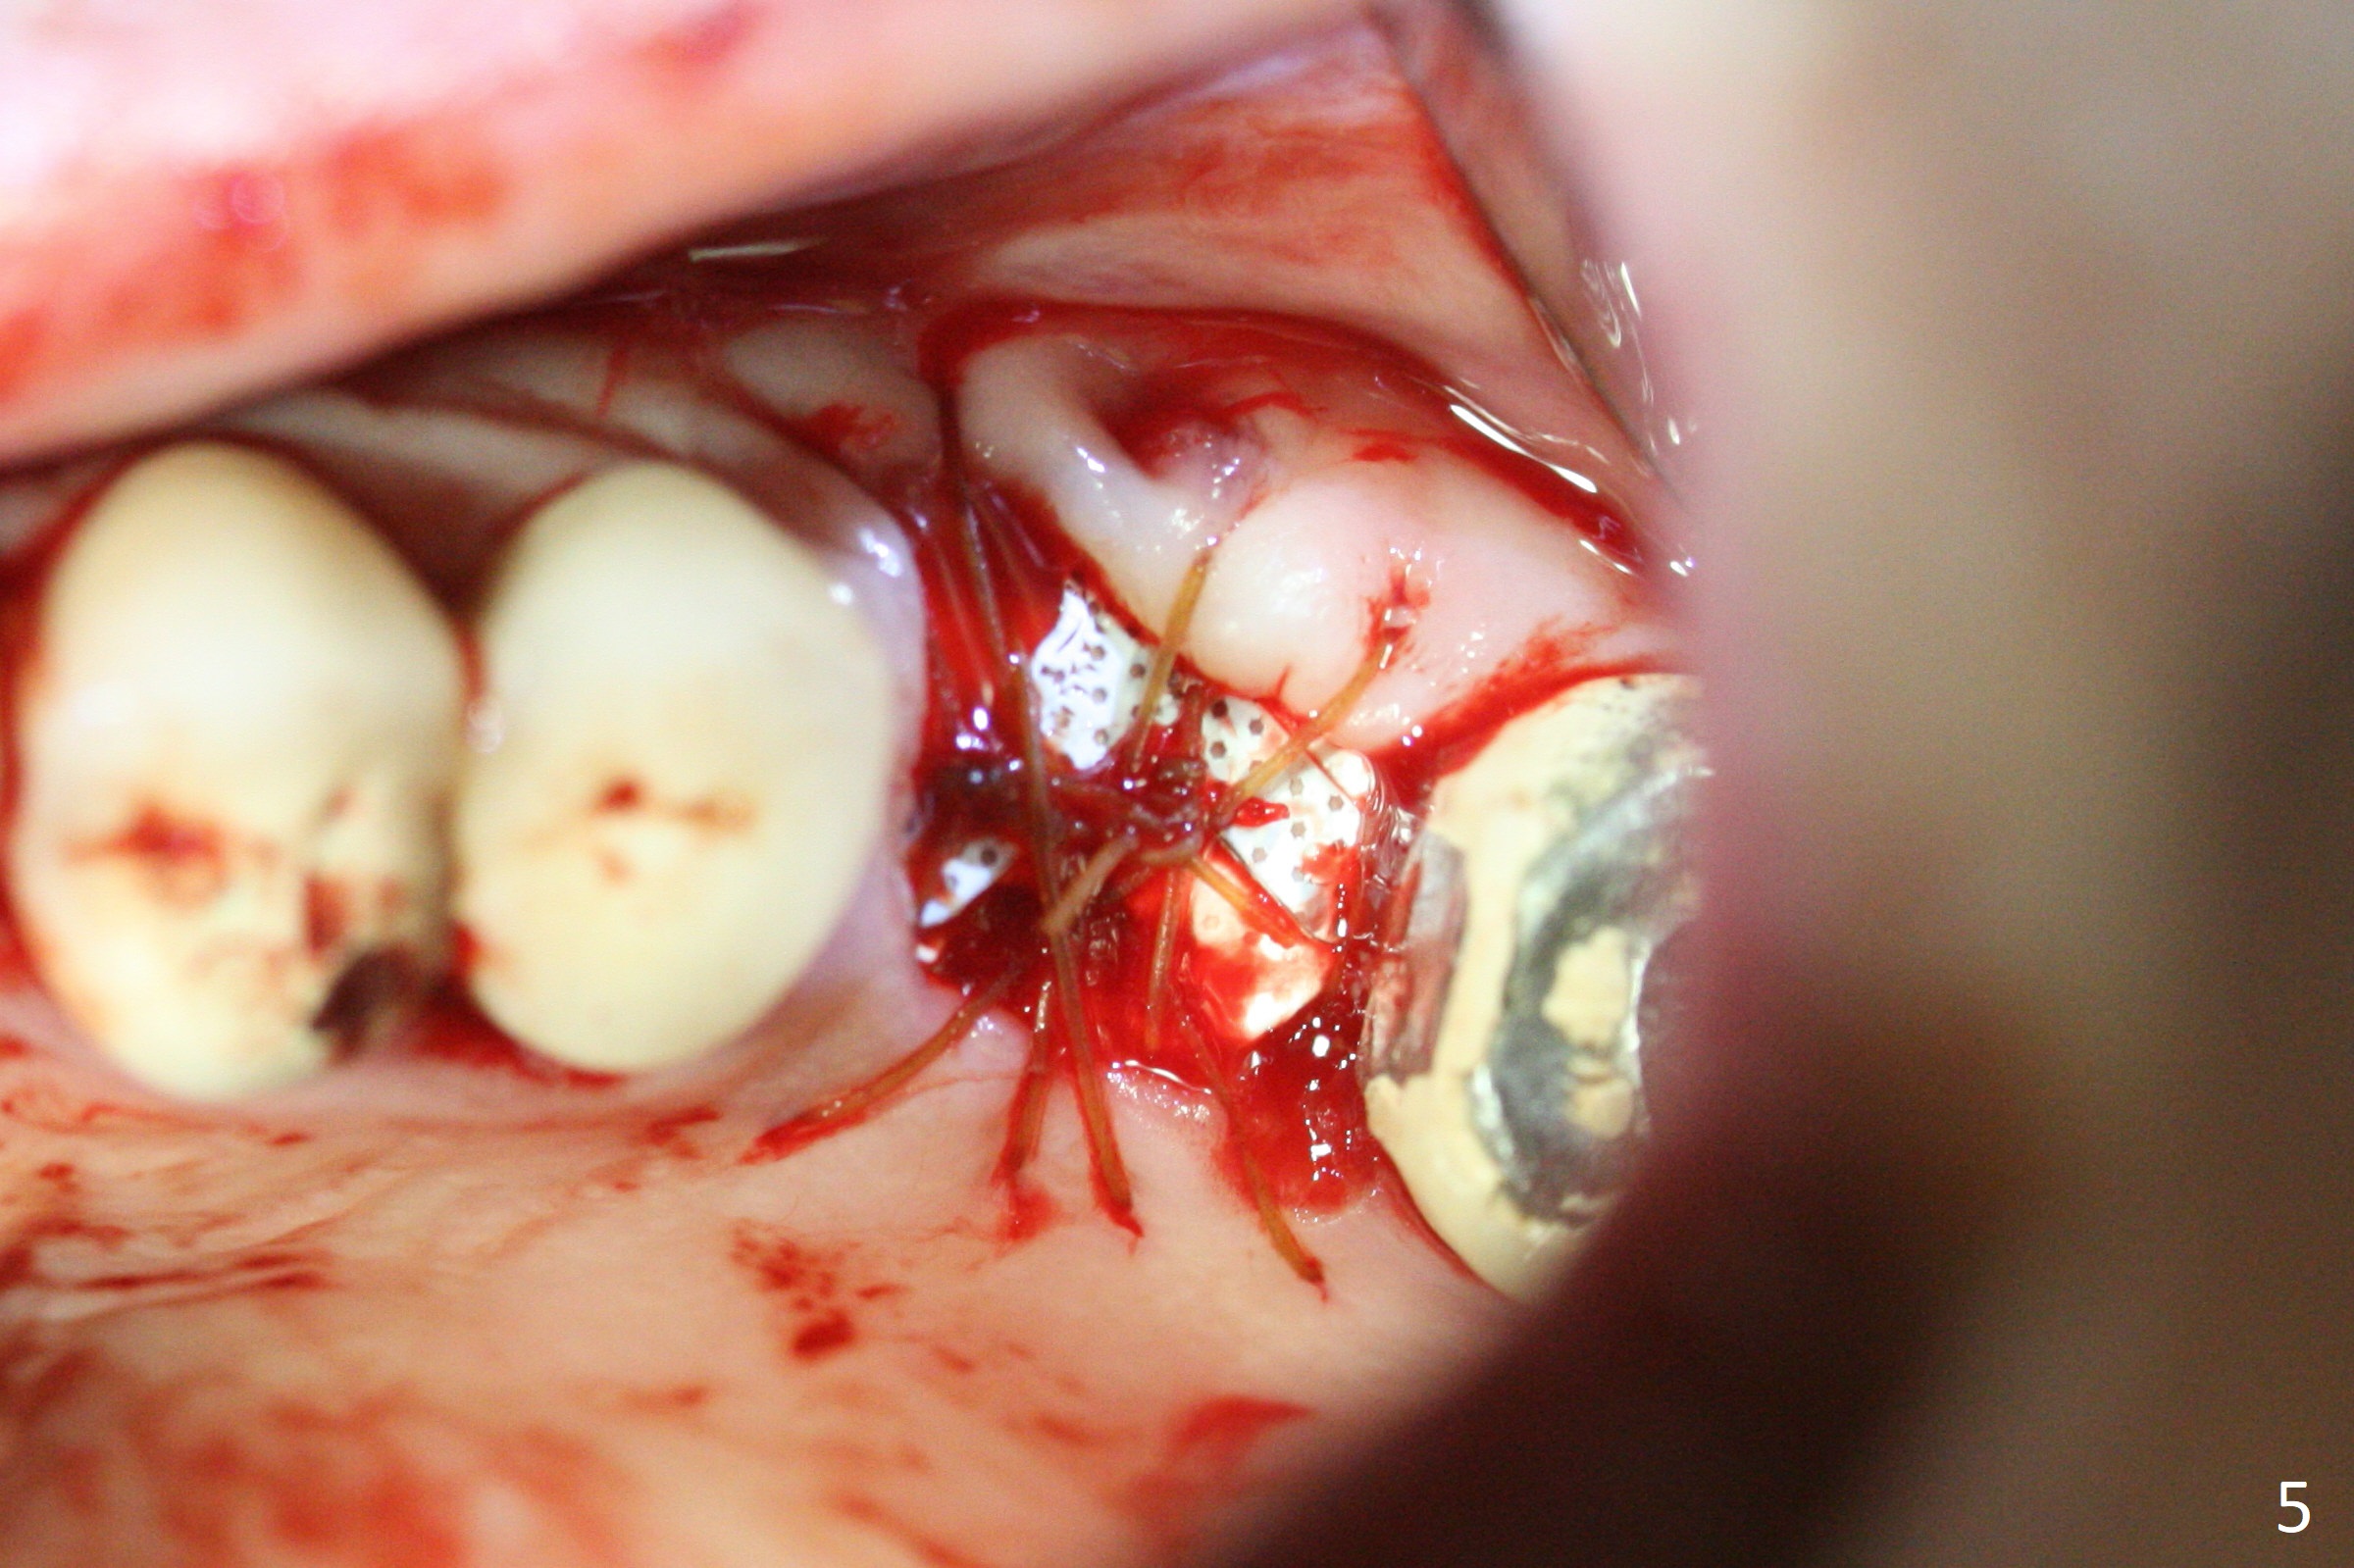

A 49-year-old woman returns for removal of the tooth #14 with loss of the buccal plate (Fig.1 red dashed line). After extraction, the buccal gingiva collapses as a dimple (Fig.2 ^). Cytoplast, a Titanium-Reinforced Non-resorbable Membrane (Fig.3), is used after bending (Fig.4) to assist in repair of the buccal plate with bone graft (Fig.5,6). As compared to Fig.1, the bone height also increases. Periodontal dressing and Cytoplast dislodge with odor 10 days postop (Fig.7,8). Periodontal dressing is re-applied. Spacer or acrylic dressing should have been used for security. In spite of the narrow ridge 5 months postop (Fig.9), a 5x11.5 mm bone level or 5x17 mm tissue-level implant is possible (Fig.10). But the implant should be placed more palatal, away from the buccal defect!